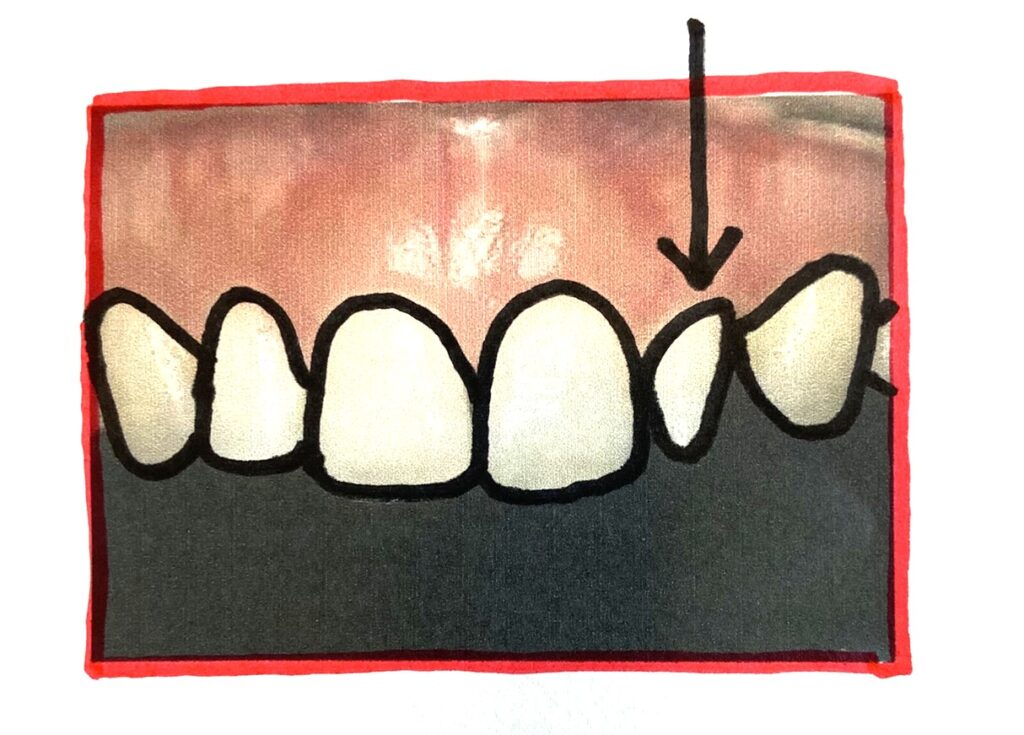

歯の形態異常の矮小歯

矮小歯(わいしょうし)というのは歯の形態異常の一つで、歯が普通の形態よりも形が小さく蕾の様な形だったり、円柱の様な形だったりします。乳歯と同程度の形の場合もあります。形が小さいがゆえに歯並びに影響を及ぼすことがあり、時として歯の間に隙間が出来るので中には気になっている方もいるかもしれません。今回は矮小歯の治療方法を含めて確認してみたいと思います。

矮小歯が出やすい部位としては、上顎の前から数えて2番目の歯(側切歯)です。また親知らずも矮小歯になることもあります。

矮小歯は形態が通常と異なり小さく、形も蕾状だったり、円柱だったりします。

そのため、他の歯との大きさのバランスが悪くなり、見た目が悪くなります。

形が小さい為、中には歯と歯の間に隙間があり気になる方もいるかもしれません。